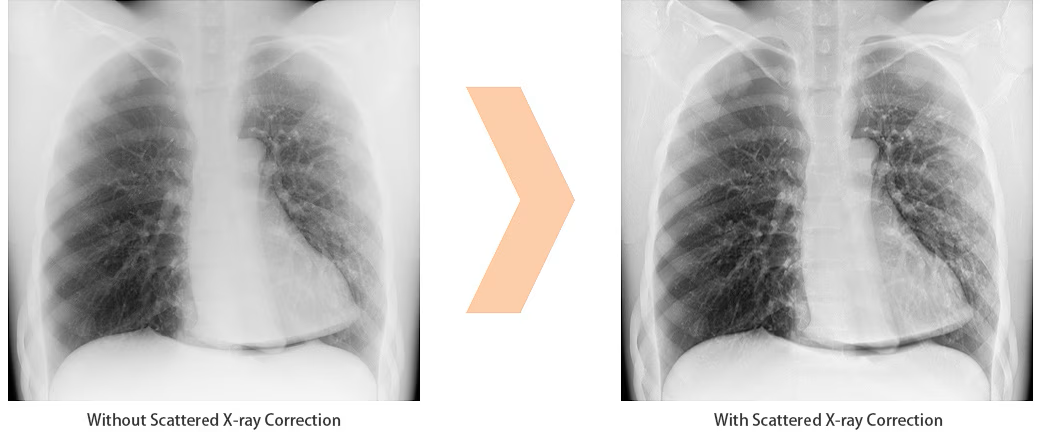

Scatter Correction: softwaregesteuertes Streustrahlenraster OPTION

Die Scatter Correction Software ist eine digitale Technik, mit der durch Streustrahlung verursachte Artefakte in einem Bild entfernt werden. Bildqualität, Kontrast und Genauigkeit werden verbessert. Zudem reduziert sich das Gewicht des Detekotors und vereinfacht die Postionierung, beispielsweise bei Untersuchungen von Patienten im Krankenbett.